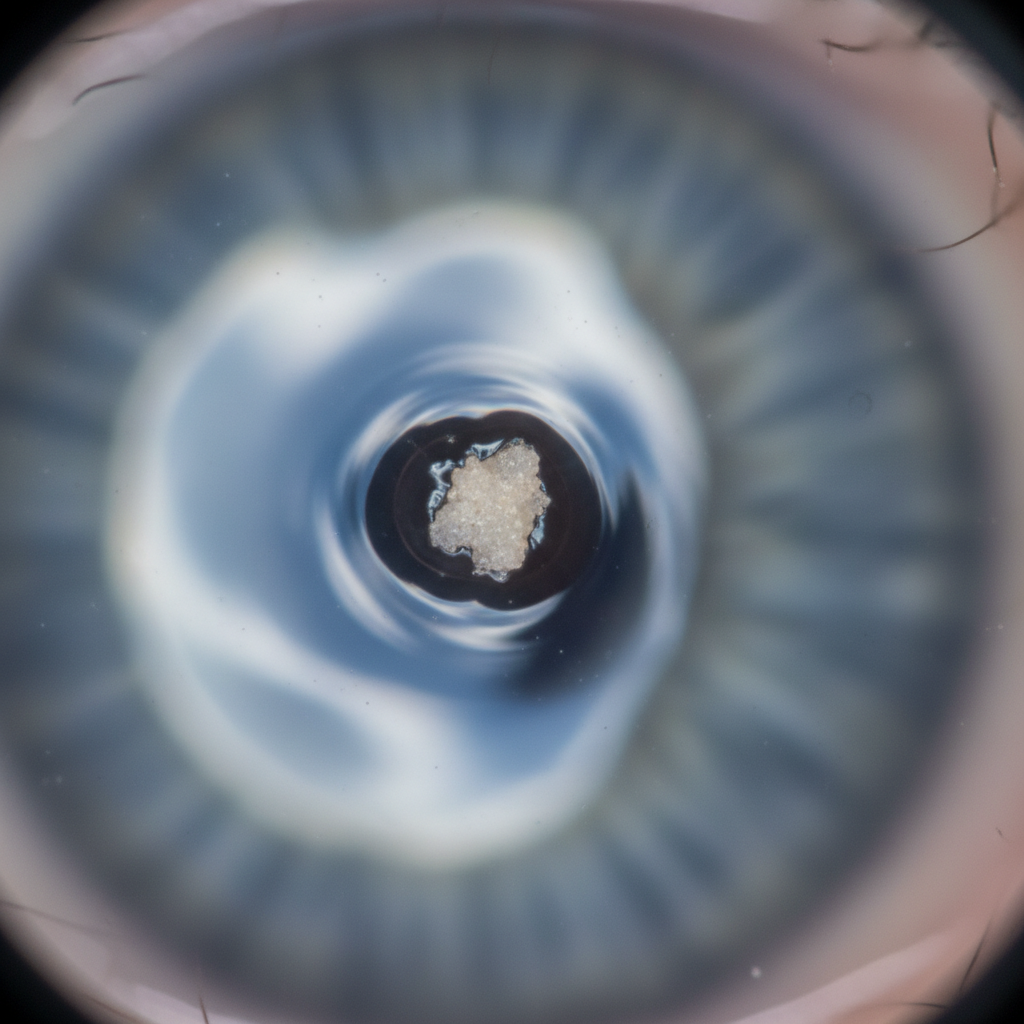

- 각막염: 결막염보다 심각한 경우로, 눈의 검은 동자를 덮는 각막에 염증이 생긴 거예요. 통증과 함께 심한 이물감, 시야 흐림 등을 유발합니다. 이 부분은 정말 조심해야 해요.